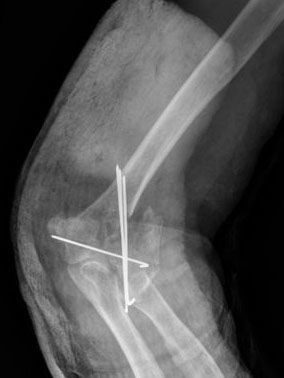

Fractura supracondílea de codo.

Fractura supracondílea de codo.Tras reducción y osteosíntesis.

Fractura supracondílea de codo. Tratamiento con agujas.